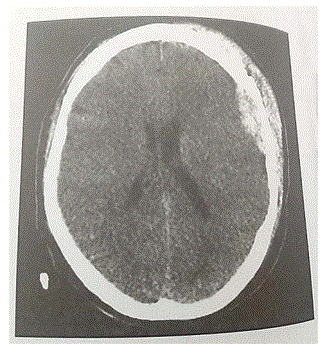

Com base na imagem tomográfica do paciente, confirma-se o diagnóstico de hemorragia subdural, caracterizada pelo acúmulo de sangue abaixo da camada meníngea da dura-máter e acima do revestimento aracnoideo do encéfalo.